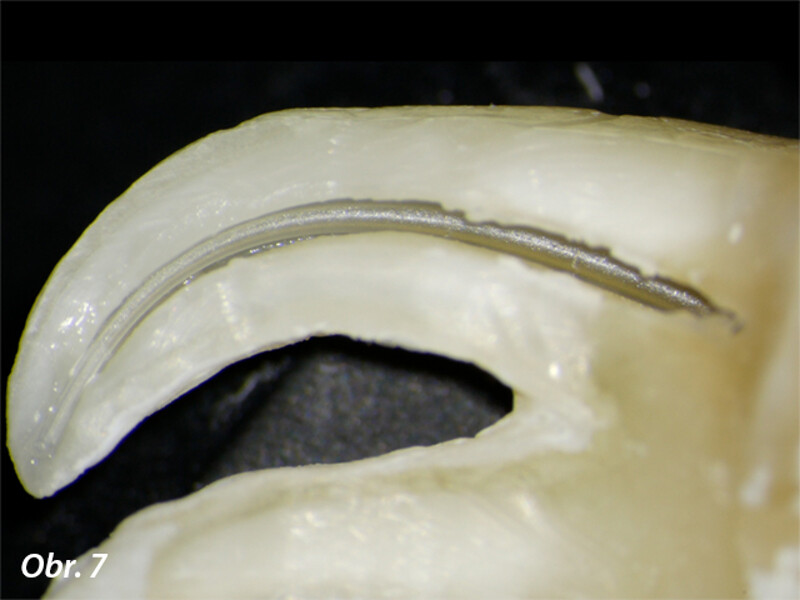

Vyplachování zahnutých kanálků